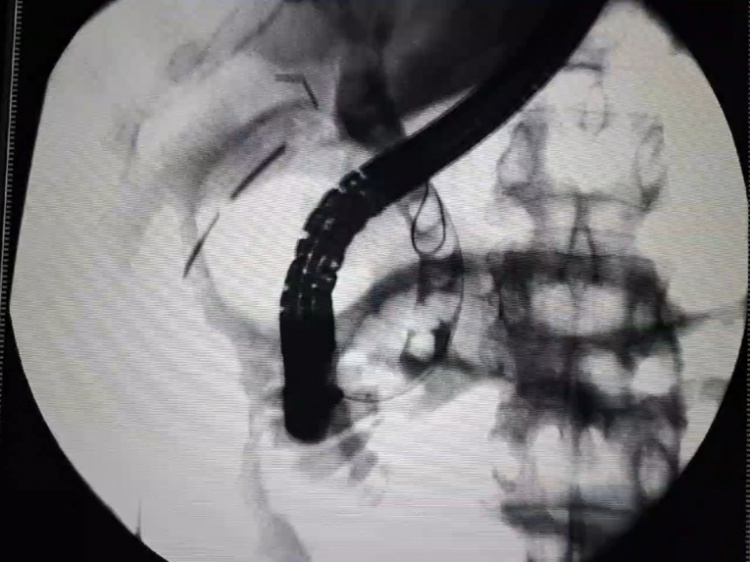

Хирурги клиники № 1 Волгоградского медуниверситета провели операцию пациентке с синдромом Мириззи.

Это редкое осложнение желчнокаменной болезни может протекать бессимптомно и приводить к механической желтухе, которая создает угрозу жизни пациента. Как сообщили Волжский.ру в ВолгГМУ, волгоградские медики впервые выполнили одномоментное лапаро-эндоскопическое лечение. Пациентке удалили желчный пузырь, извлекли конкременты из магистральных желчных протоков, восстановили нормальный желчеотток и осуществили первичный шов гепатохоледоха.

Операция длилась 2,5 часа. При этом пациентке не придется проходить длительное наружное дренирование желчных протоков в послеоперационном периоде.